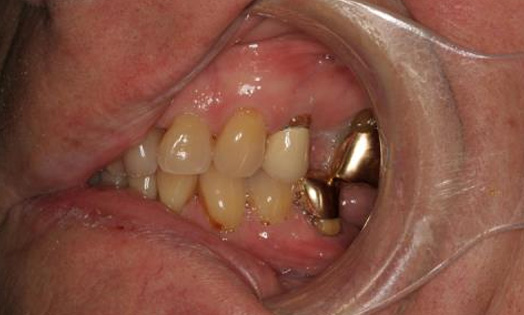

Intraoral clinical exam

- Teeth with exposed root surfaces from gingival recession

- Discoloration of teeth

- Supraerupted teeth

- Abfractions

- Wear facets on posterior teeth and restorations

- Gold crowns

- #s 2, 14, 15, 20, 30

Final Intraoral Photographs